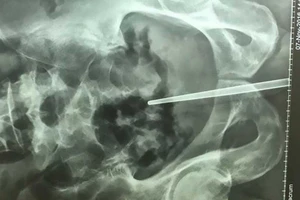

Chơi dại nhét đũa vào dương vật